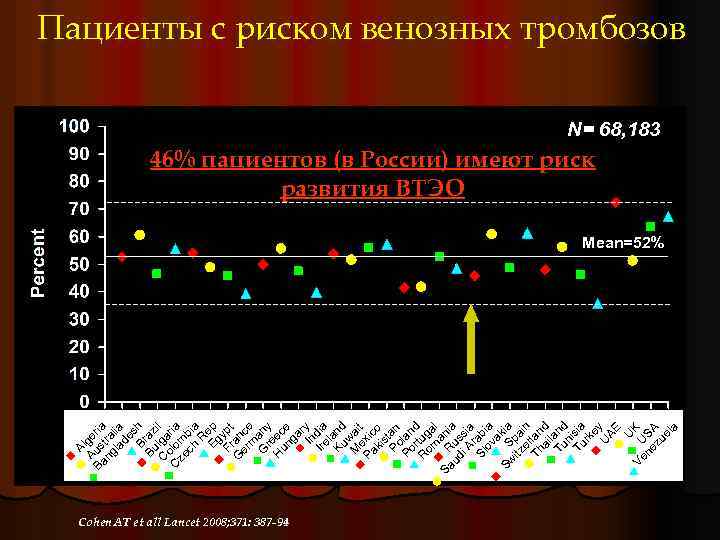

U Ve U K ne SA zu el a A Au lge Ba s ria ng tra la lia de s Br h Bu az C lga il C olom ria ze ch bia R Eg ep Fr ypt G an er ce m G any r H eec un e ga r In y Ire dia l Ku and w M ai ex t Pa ic ki o s Po tan Po lan r d R tug om a l Sa R ani ud us a i A sia r Sl ab ov ia a Sw S kia itz pa e in Th rlan ai d l Tu and n Tu isia rk e U y AE Пациенты с риском венозных тромбозов N= 68, 183 46% пациентов (в России) имеют риск развития ВТЭО Mean=52% Cohen AT et all Lancet 2008; 371: 387 -94

Результаты ENDORS в России l Риск ВТЭ выявлен у 45, 7% пациентов У 52% хирургических l У 36. 7% терапевтических l l Профилактика проводилась только у 23, 8% пациентов l Более чем в 2 раза ниже среднего уровня мирового показателя l Примерно на одном уровне с Пакистаном, Индией и Венесуэлой